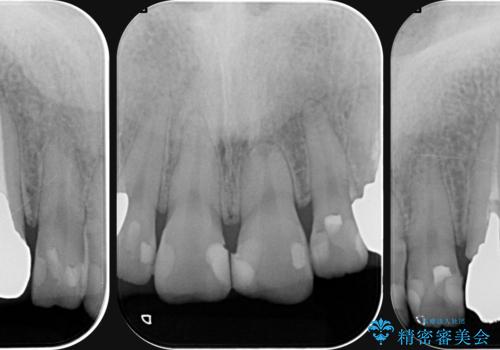

複数箇所コンポジット充填された前歯をセラミック治療

- コンポジットレジンの充填箇所がすり減ってしまい、形の悪くなった前歯の治療を希望され来院されました。

充填部位が大きく、再度充填をするには神経と近くなり抜髄のリスクが高まるため、劣化の少ないセラミックでフルカバーするセラミッククラウン治療を行うこととしました。

前歯の小さな虫歯は、除去したのちコンポジットレジンと言われる樹脂を充填する処置を行うことが多々あります。

しかし、経年劣化が早く着色や小さな虫歯が再発しやすいため、ある程度の大きさになってしまった場合セラミッククラウンで置き替えた方が神経を温存し長期的な予後の期待できる治療となります。